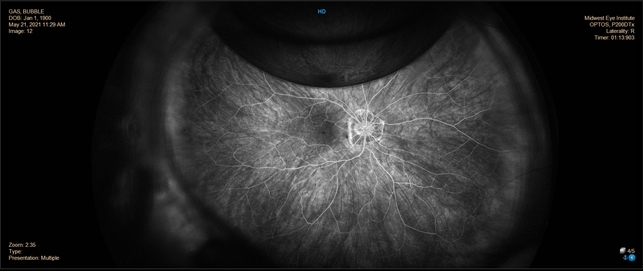

Intravitreous Gas Bubbles Retina Image Bank